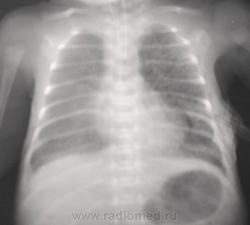

На первых снимках левосторонний пневмоторак; затем дренирование, пневмоторакс, практически, разрешился, признаки РДС  новорожденных (отек).

Не УЗИкают у нас. РДС поставил, был вопрос о пневмонии, но я ответил отрицательно. Слева посткомпрессионная пневмония имеется (спор с неонатологом)?

На последих 3-х снимках явления подкожной эмфиземы. ИМХО: смещение средостения и коллабирование лёгкого являются следствием пневаторакса, причина которого, вероятно в незрелости лёгочной ткани.